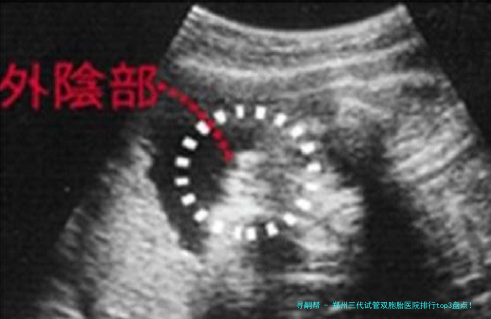

三代试管技术如何科学规划双胎?

很多人好奇:三代试管真正能""孪生儿吗?谜底是:可以科学方案,但不行确保!关键在于胚胎筛选和移植策略。

双胚胎移植:一次移植两个优质胚胎,增加双胎概率

胚胎体外培养:将胚胎培育至第五日至六日,检查筛选具发育潜能的胚胎